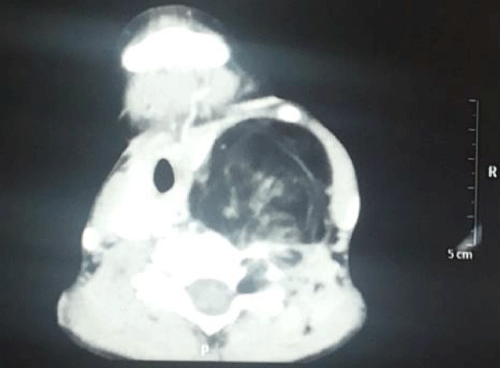

Contrast enhanced computed tomogram showed 10.2cmx5.5cmx5.2cm, large, uncapsulated diffusely infilterative lipomatous mass showing multiple thin and thick septations with nodularity. Superomedially the mass was extending into the parapharyngeal space and deviating the left oropharynx airway towards right. Posterosuperiorly the mass was extending in the prevertebral region with extension into the cervical neural foramina and foramen transversarium at C4-5; C5-6;C6-7 levels, causing widening of neural foramina with thinning and scalloping of adjacent pedicles and lamina (Figure 3). Anterosuperiorly the mass is displacing the carotid sheath anteriorly and medially the esophagus, larynx, trachea and thyroid gland were displaced contralaterally with no luminal narrowing. Inferiorly, small extension was seen into the superior mediastinum with splaying at the origin of left common carotid artery and left subclavian artery (Figure 4).

Figure 3:

Figure 4: